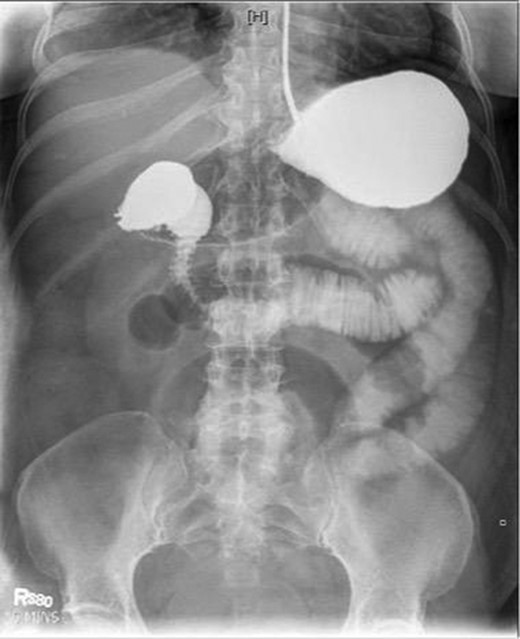

Laboratory studies were remarkable for leukocytosis, and an elevated lactate that improved with hydration (Fig. 1), while urinalysis was unremarkable. Abdominal CT scan obtained at this time demonstrated a partial SBO in the mid-small bowel as well as inflammation and thickening of the duodenum. A small bowel series was ordered, and showed high grade SBO (Figs 2–5).

Fluoroscopic barium study demonstrating oral contrast agent progression through the small bowel at 30 min after ingestion.